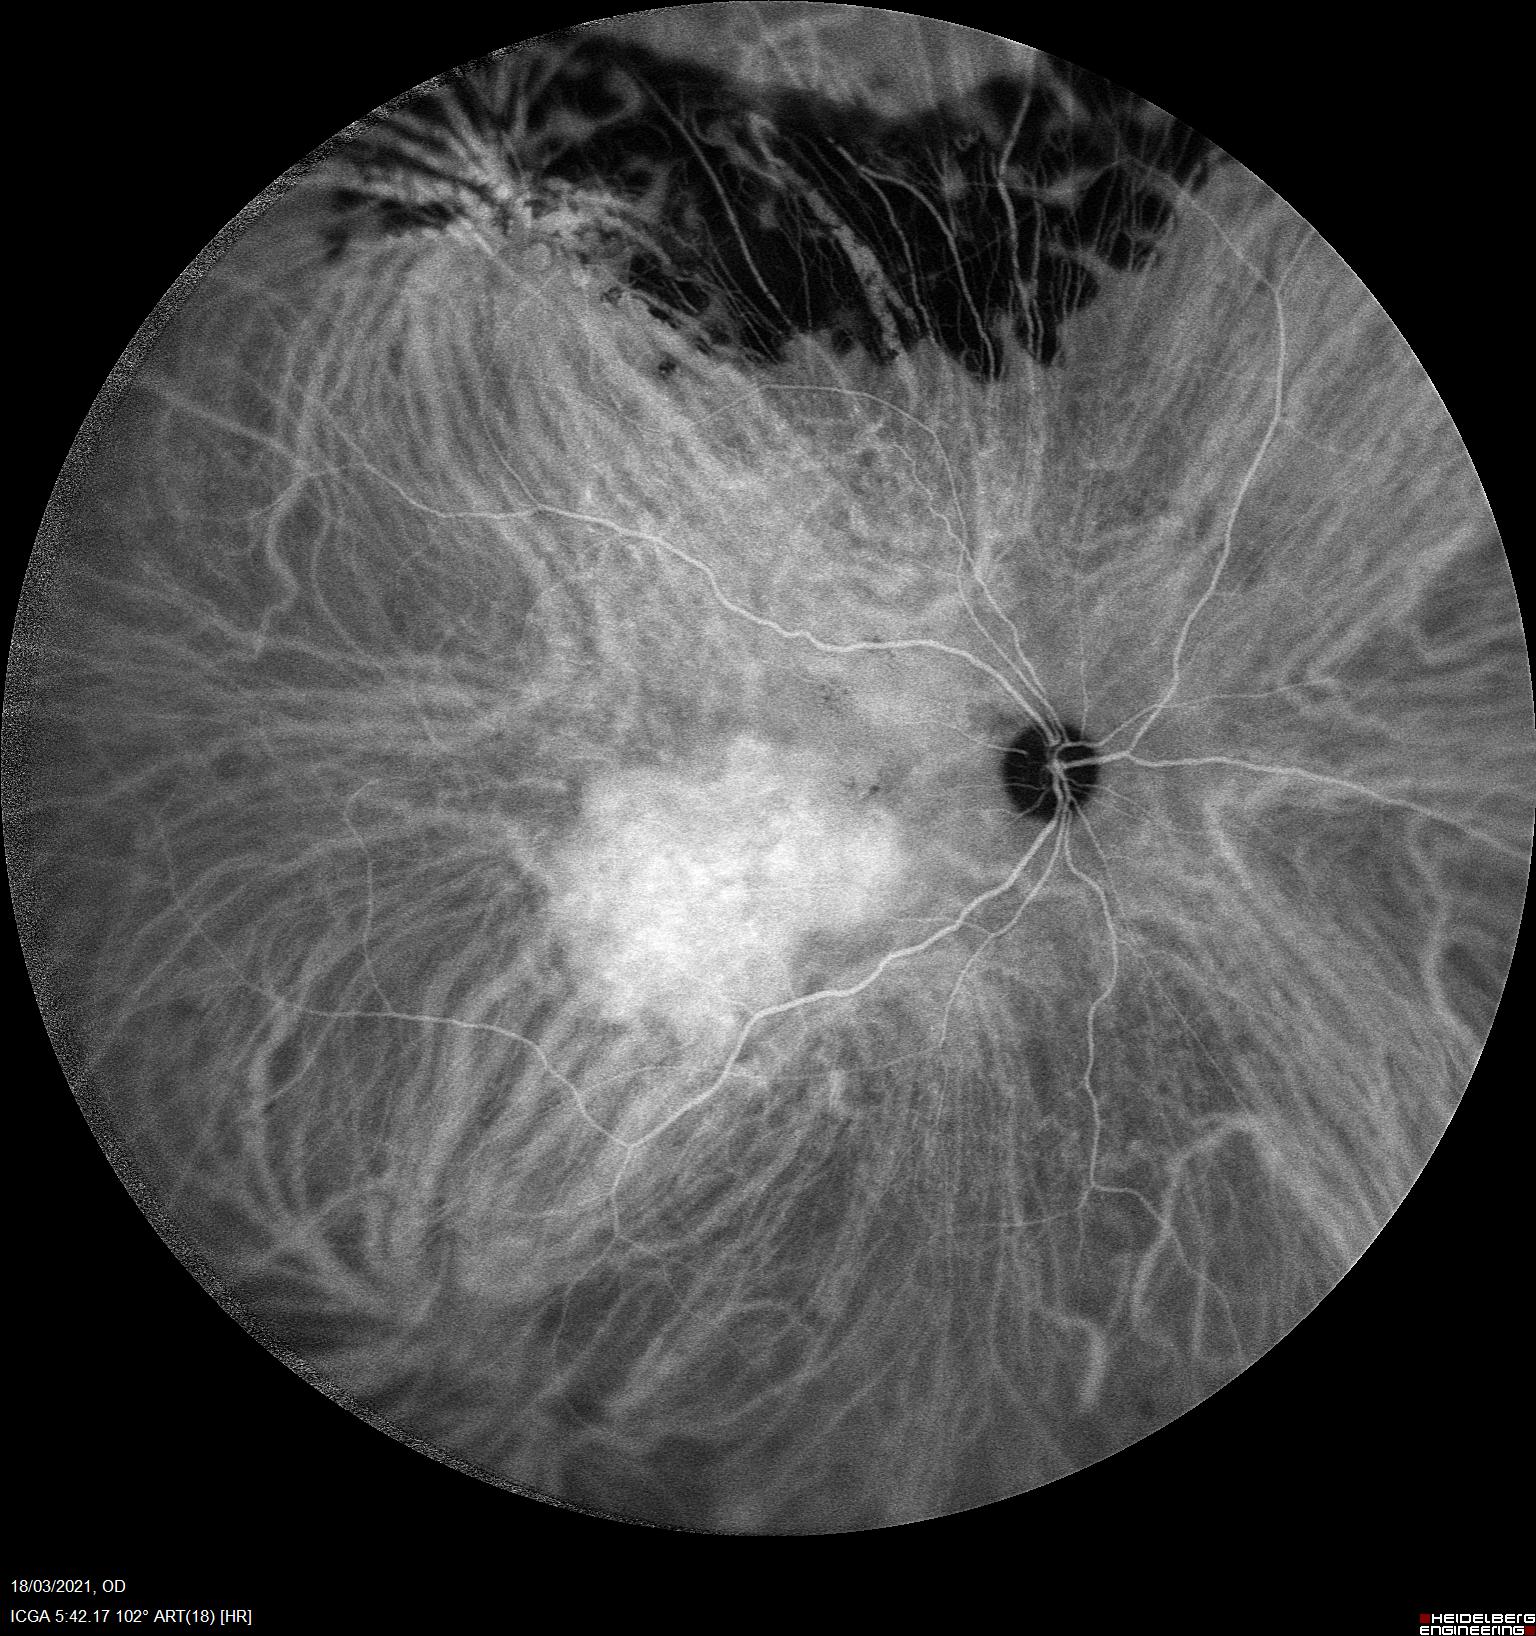

Una de las herramientas más útiles para su diagnóstico es la angiografía con verde de indocianina.

En la ICV podemos apreciar una hipercianescencia precoz con una iso/hipocianescencia tardía que refleja el alto flujo vascular y capacidad de lavado que presentan estos tumores vasculares a diferencia de otros funduscopicamente similares.